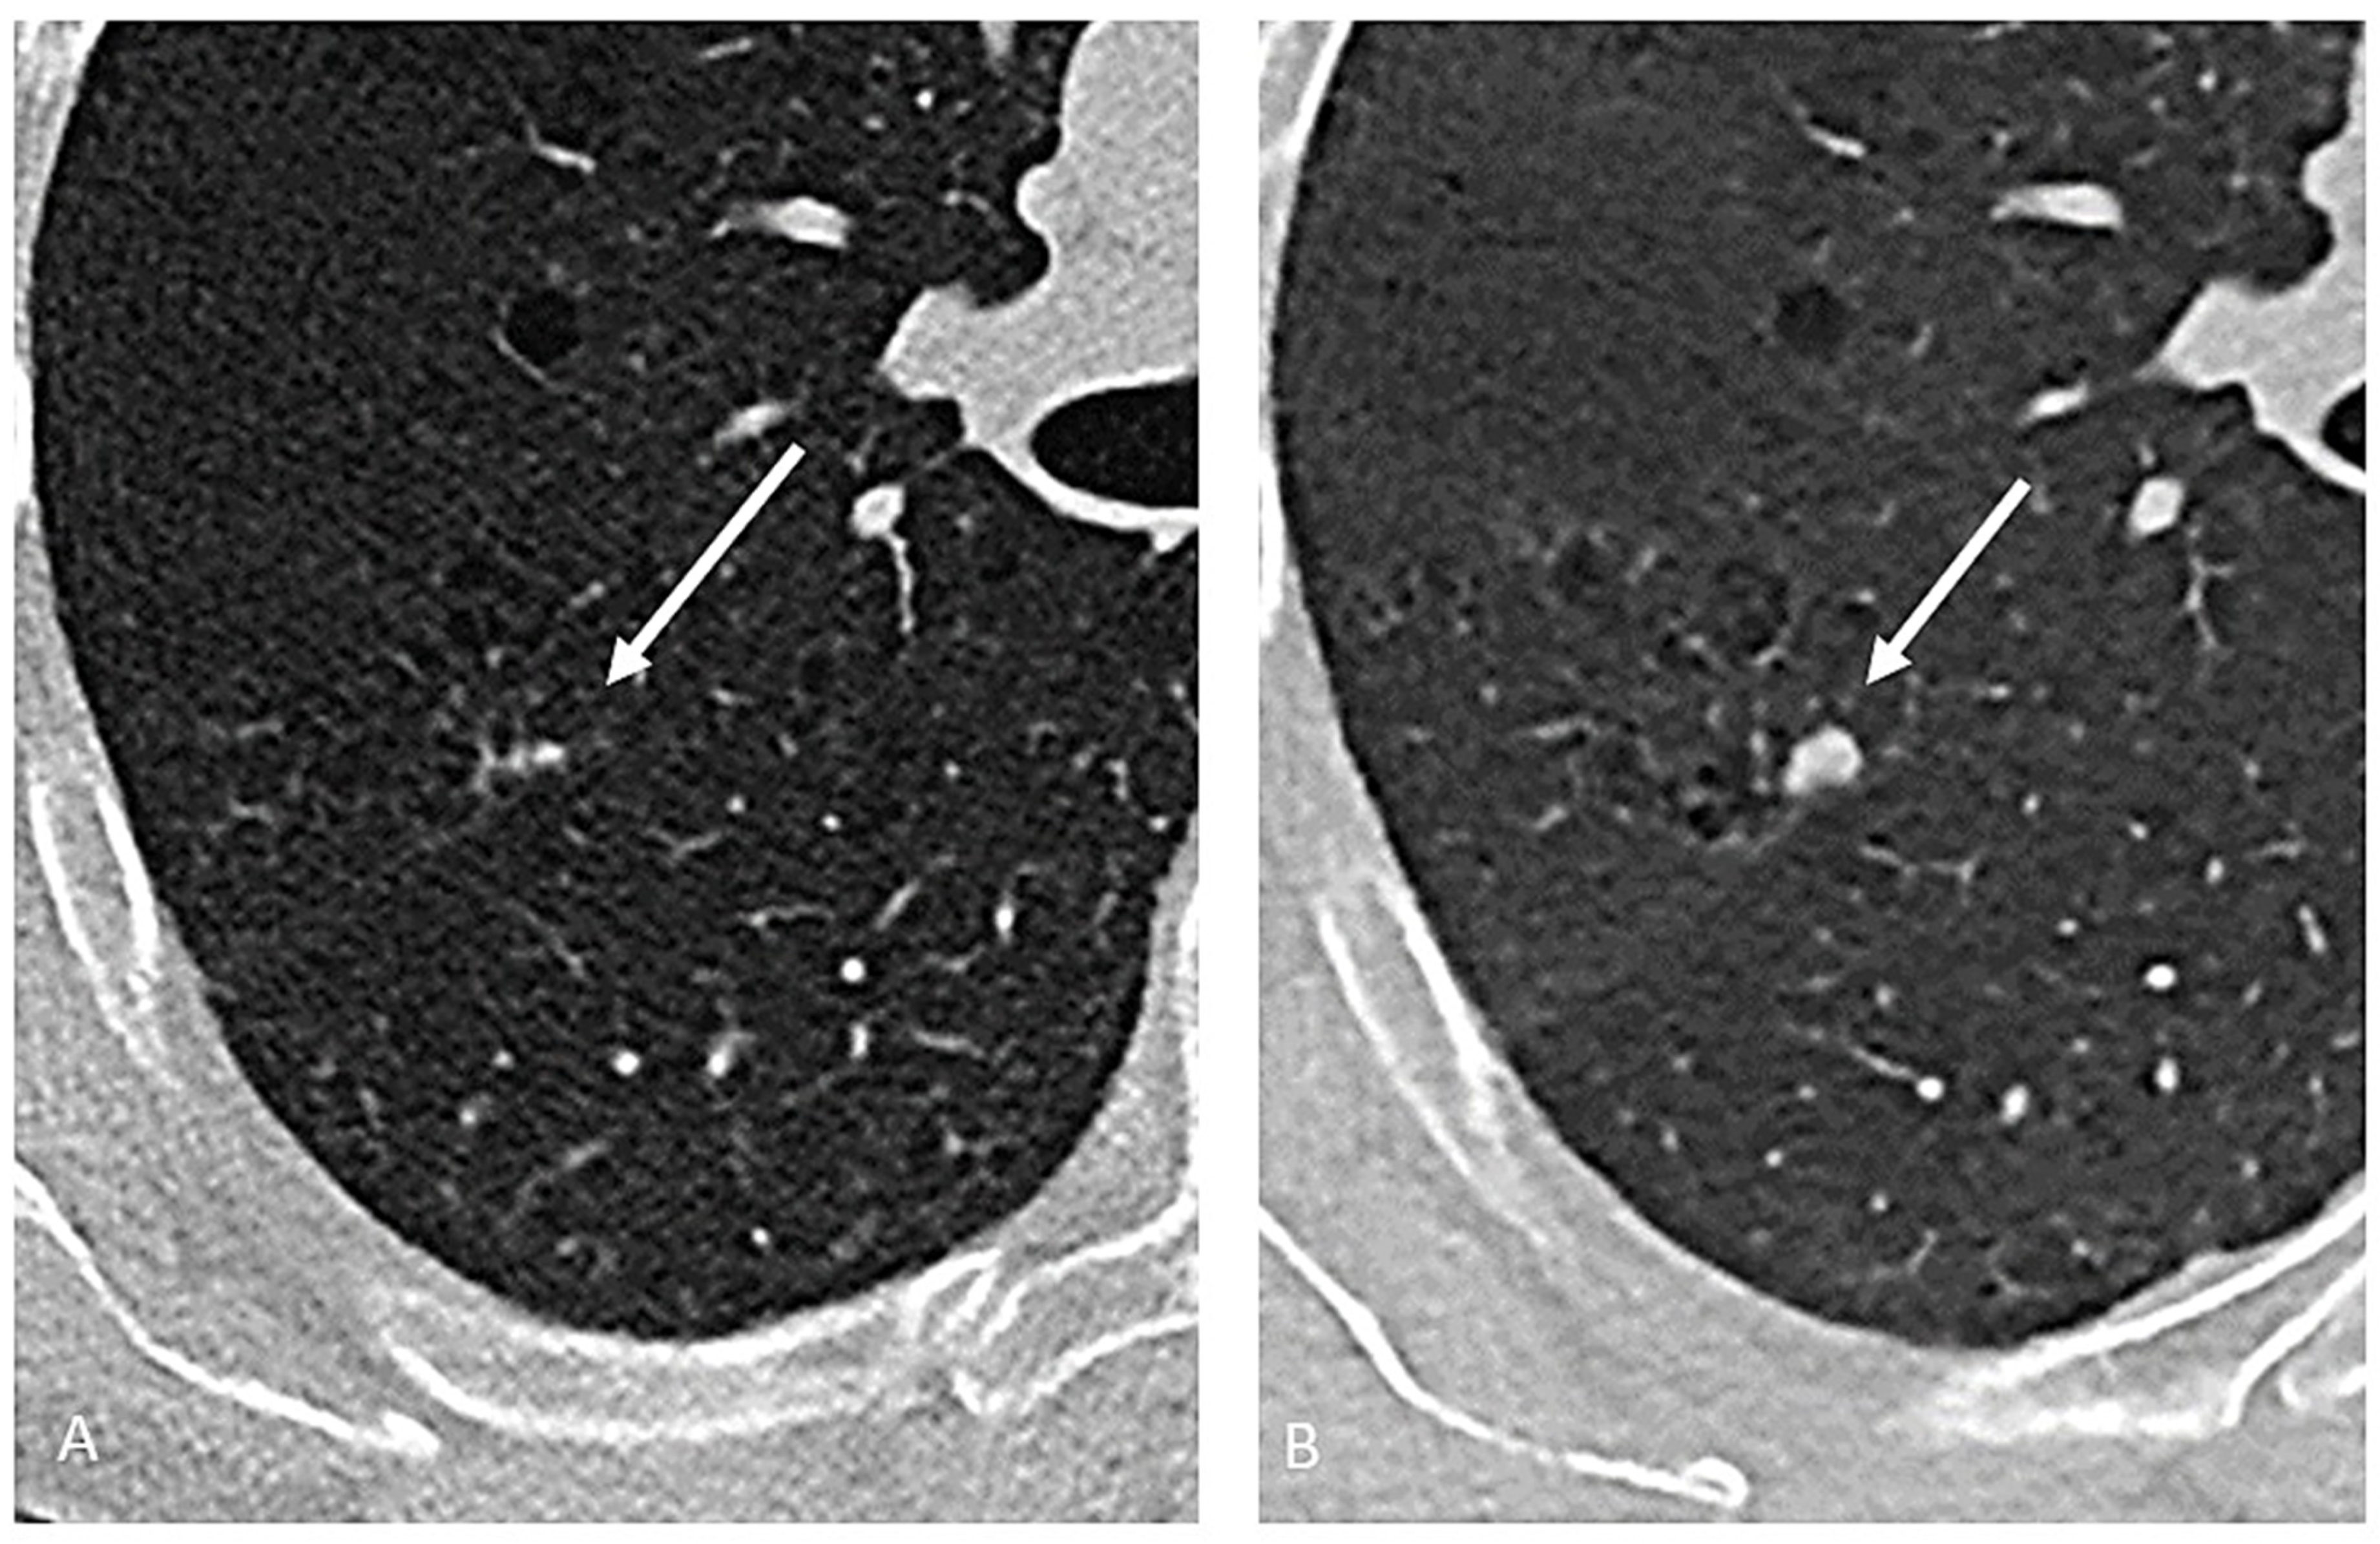

5. Tissue Sampling—CT-Guided Biopsy